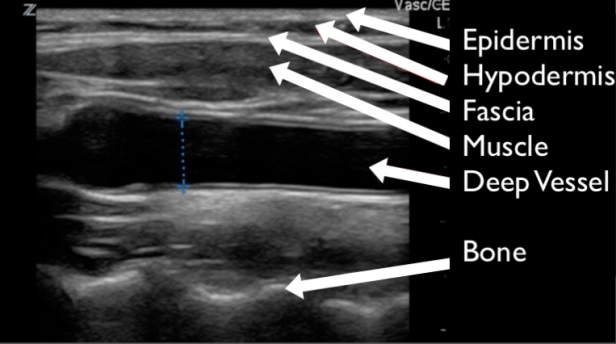

CEllulitis - CobbleStoning

Tutorial: http://5minsono.com/softtissue/

Abscess

Evidence: https://bmjopen.bmj.com/content/7/1/e013688